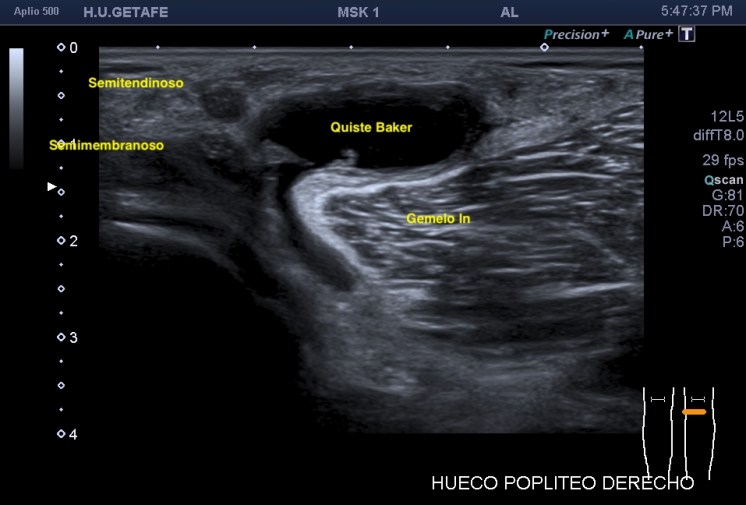

En la imagen 1 su anatomía, que es primordial y además me tiene loco perdido. El Gemelo y el Semimembranoso, profundo al Semitendinoso, que si los continuas en eje corto hacia próximal van a ser dos supermúsculos de la parte posterior del muslo. Y el cuello, del quiste que es muy bonito también.